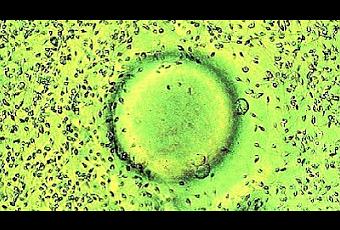

Con un grupo de mas de 1000 profesionales podemos ver varias técnicas en la Fecundación in Vitro, entre ellas destacamos a la estimulación ovárica, la punción y laboratorio, fecundación de óvulos y el cultivo embrionario. No esperes más, conoce desde nuestro sitio Web con detalles cada uno de nuestros servicios para que puedas cumplir tu sueño de ser madre.